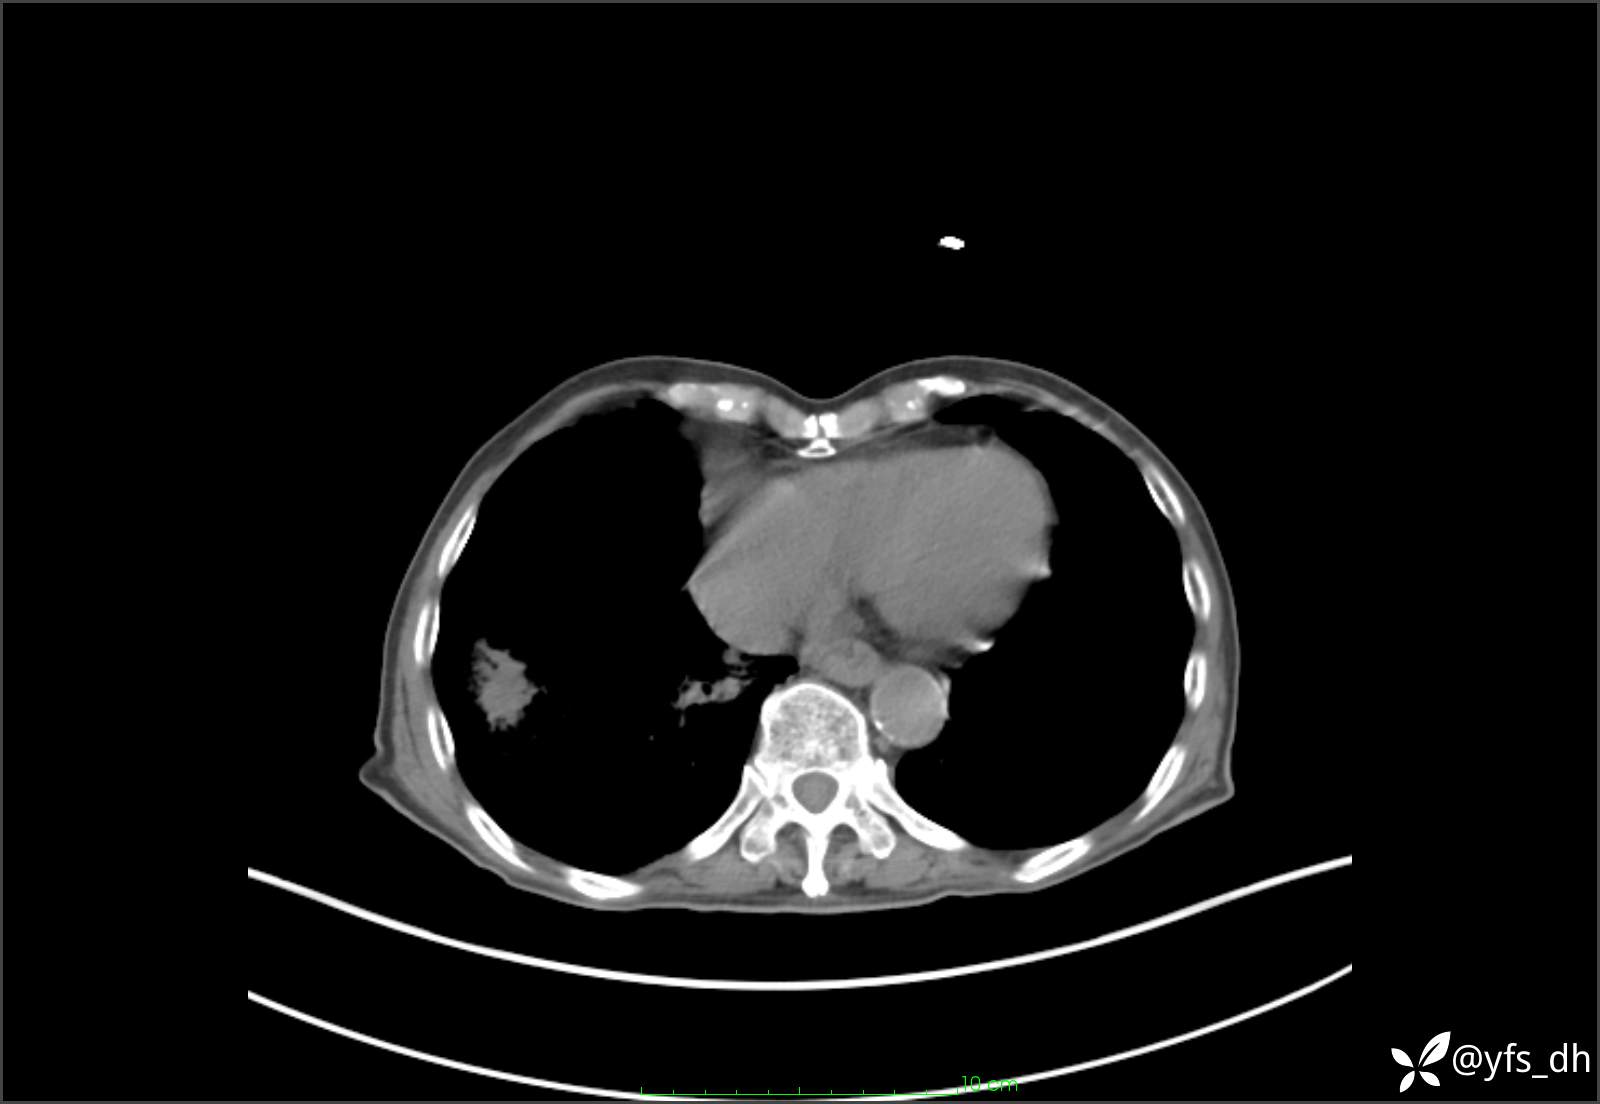

1.简要病史:患者4天前突发上腹部疼痛不适,但可以忍受。3小时前饭后突然加重,不能忍受后就诊。

2.简要手术记录:术中见腹盆腔大量肠液及粪便,乙状结肠中下段见一约3cm的破口。